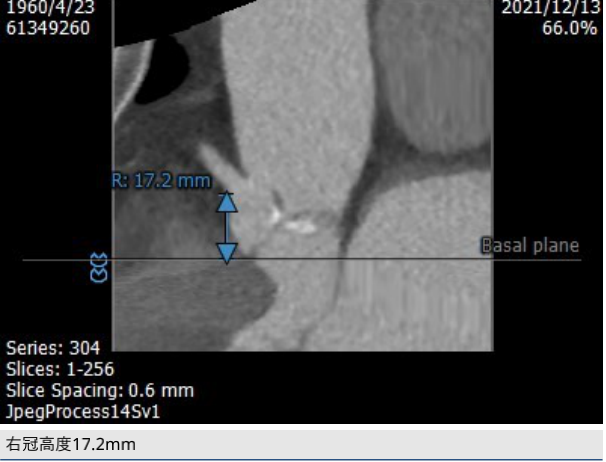

CT评估: